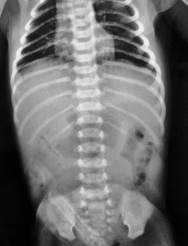

Se solicitó radiografía de abdomen (Figura 2), que mostraba presencia de aire a nivel del estómago con escaso gas distal.

Figura 2: Rx de abdomen. Nótese la presencia de aire a nivel gástrico con la prácticamente ausencia de gases distales.

En cuanto a los estudios de imágenes, si bien la radiografía simple de abdomen puede tener cierta utilidad para plantear la sospecha clínica, cuando se encuentra distensión gastro duodenal -eventualmente con niveles hidroaéreos-, y ausencia de gases distales al duodeno comprometido en el pie del vólvulo, como se esboza en nuestro segundo paciente (no hay dilatación, pero si franca disminución de los gases distales), la misma es muy inespecífica y puede no aportar ningún elemento orientador, como ocurrió en nuestro primer paciente, que presentó una radiografía de abdomen con distensión gaseosa sin niveles hidroaéreos de todo el intestino, que incluso llegaba a simular un marco cólico normal, y en la que tampoco se apreció neumoperitoneo, a pesar de la perforación intestinal comprobada luego durante la cirugía.